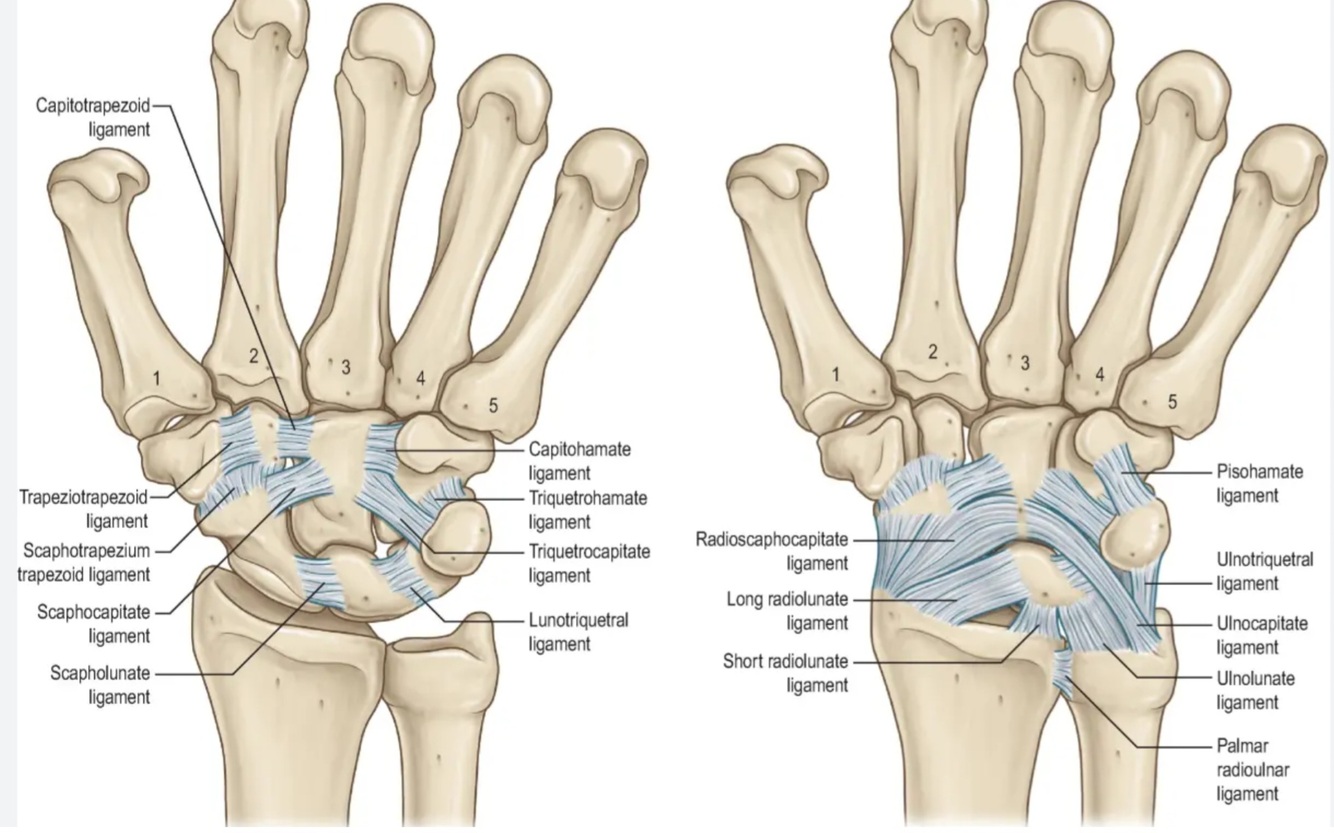

Luxation du poignet (petit arc) = luxation péri-lunaire du carpe

Dans quel ordre va rompre les ligaments péri-lunaires?

radio-lunaire

scapho-lunaire

capito-lunaire

luno-triquetal

A

1. scapho-lunaire

2. capitolunaire

3. luno-triquetral

4. radio-lunaire

rechercher atteinte nerf médian